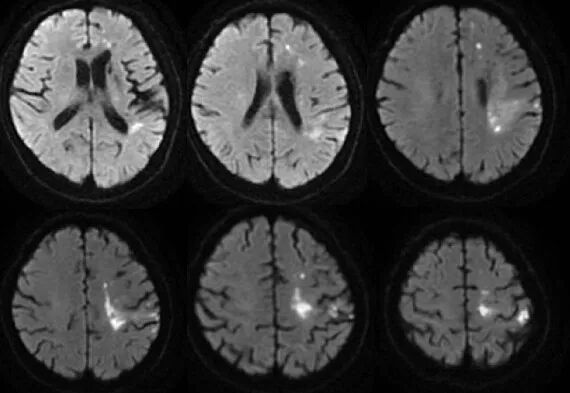

入院影像检查

导丝怎么扩【载药时代 球扩天下】NOVA DES®颅内药物洗脱支架在颅内富穿支区域使用体会二例!_https://www.jmylbn.com_新闻资讯_第10张

MRA

导丝怎么扩【载药时代 球扩天下】NOVA DES®颅内药物洗脱支架在颅内富穿支区域使用体会二例!_https://www.jmylbn.com_新闻资讯_第11张

DWI

重要影像结论:左侧额顶叶梗死灶(急性或亚急性期),较3月前明显增大,左侧大脑中动脉闭塞。

导丝怎么扩【载药时代 球扩天下】NOVA DES®颅内药物洗脱支架在颅内富穿支区域使用体会二例!_https://www.jmylbn.com_新闻资讯_第12张

导丝怎么扩【载药时代 球扩天下】NOVA DES®颅内药物洗脱支架在颅内富穿支区域使用体会二例!_https://www.jmylbn.com_新闻资讯_第13张

ASL

重要影像结论:ASL示:原左侧额颞顶枕叶、右侧颞枕顶叶血流灌注量明显减低区范围较3月前明显增大。